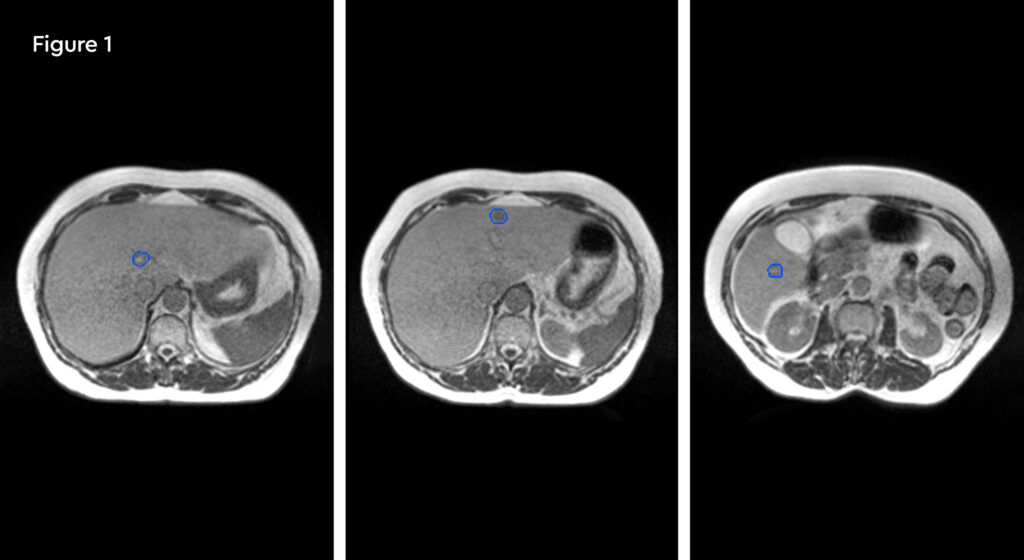

A 52-year-old female with metastatic renal carcinoma. At the time of referral for stereotactic ablative radiotherapy (SABR) she had oligoprogressive disease in a single lymph node beneath the right diaphragmatic crus (figure 1).

The patient was initially diagnosed in October 2018 when she also underwent an open right radical nephrectomy confirming the presence of renal clear cell carcinoma with rhabdoid change, stage T3bNxMx. Further investigation revealed the presence of multiple pulmonary metastases and she was commenced on nivolumab and ipilimumab immunotherapy treatment. Her metastatic disease had been completely controlled with no evidence of growth until a routine check CT scan identified an enlarging right upper abdominal node adjacent to the right diaphragmatic crus. At the same time, she developed right upper abdominal pain which was thought to possibly be due to the nodal growth but also possibly due to gallstones which she was also known to have.

Fig 1: Pre-treatment CT scan showing right upper abdominal node measuring 25mm on 10th January 2020